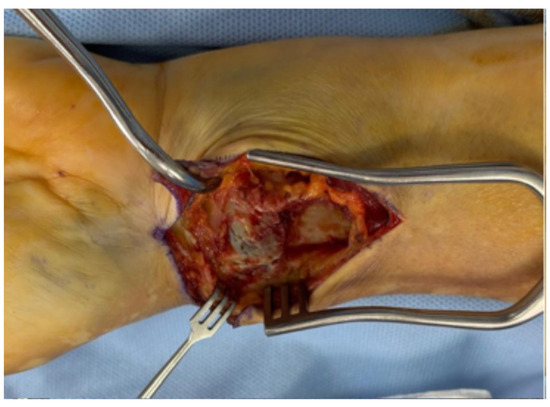

A Novel Modification of Anconeus Muscle Flap for Extensor Digitorum Communis-Selective Lateral Epicondylitis: Preliminary Clinical Study

Introduction: Lateral epicondylitis (LE) typically affects the extensor carpi radialis brevis (ECRB) tendon, while isolated degeneration of the extensor digitorum communis (EDC) origin is rare and poorly characterized. Surgical debridement of these lesions may result in capsular exposure requiring soft-tissue coverage, which can be achieved through a vascularized muscle flap to enhance tendon healing potential and reduce recurrence. This study aimed to describe a modification of the anconeus rotation flap as originally described by Almquist in 1998, and to evaluate its clinical and functional outcomes in patients with isolated EDC tendinopathy. The modified technique consists of a simpler muscle advancement (AMA) that preserves the distal vascular pedicle and reduces soft-tissue dissection. Methods: A retrospective study was conducted on 12 consecutive patients with lateral epicondylitis with isolated EDC tendon involvement (10.71% of all operative cases at our Institution between 2019 and 2022), who were surgically treated with the anconeus muscle advancement modification. Clinical outcomes, including the visual analog pain scale (VAS), grip strength and patient-reported outcome measures (PROMs), which include the QuickDASH score, the Mayo Elbow Performance Score (MEPS) and the Patient-Rated Tennis Elbow Evaluation (PRTEE) score were assessed. Paired statistical tests with 95% confidence intervals and minimal clinically important difference (MCID) thresholds were applied. Results: At a mean follow-up of 38 months, all outcomes demonstrated statistically significant and clinically meaningful improvements (p < 0.05). Reductions in pain/disability (VAS, QuickDASH, PRTEE scores) and functional gains (Grip strength, MEPS) far exceeded their respective MCID thresholds, with 100% attainment for each outcome. Conclusions: This modified anconeus muscle advancement appears to be a technically feasible option for managing isolated EDC-related lateral epicondylitis, preserving vascular integrity while limiting dissection. Although favorable results were obtained, the small retrospective cohort precludes definitive conclusions regarding efficacy. The findings support the technical feasibility of the proposed modification and warrant further prospective comparative investigations.